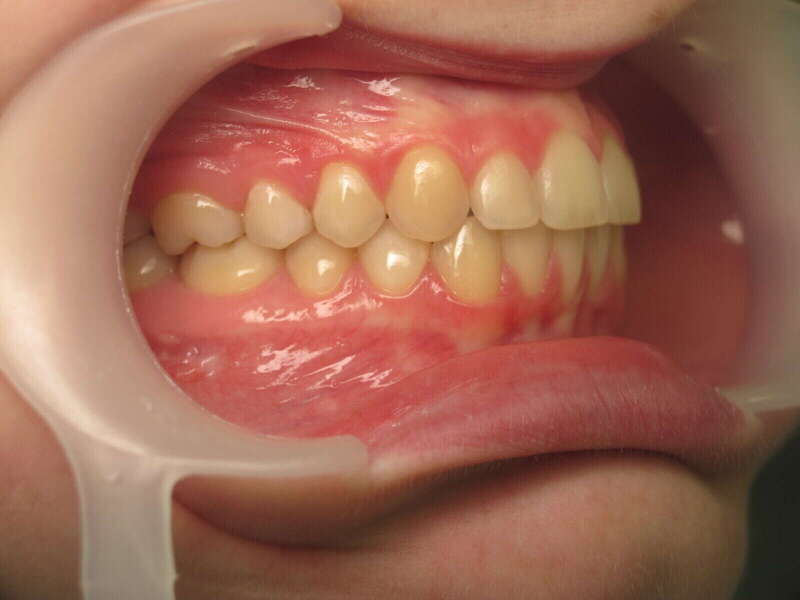

Ce cas d’interception chez un enfant de 8 ans démontre l'efficacité des aligneurs pour corriger des troubles fonctionnels précoces. Le diagnostic présentait des inversions d'articulé provoquant une déviation de la mandibule vers la gauche et un décalage des milieux.

Grâce à une coopération exemplaire et un traitement totalement indolore, l'expansion de l'arcade a permis de recentrer la mâchoire. Cette intervention a littéralement remis la croissance sur les rails, neutralisant le risque d'asymétrie faciale squelettique.

• Correction fonctionnelle : Recentrage immédiat de la mandibule et des milieux inter-incisifs.

• Prévention : Création d'un environnement favorable pour les dents définitives à venir.

• Bien-être : Approche douce respectant le confort de l'enfant.

C'est une étape fondamentale qui simplifie l'avenir orthodontique du patient tout en garantissant un développement facial harmonieux.

Avant